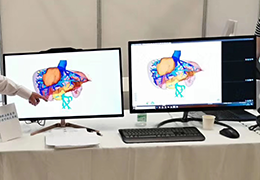

ANYTHINK 经导管主动脉瓣膜置换术分析系统